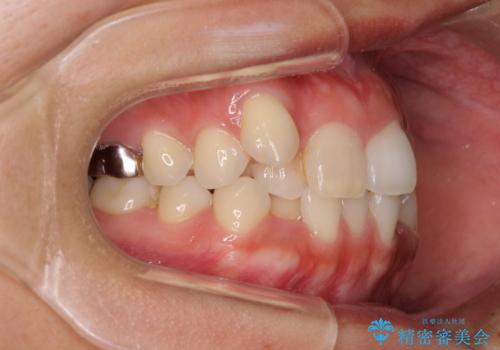

- 八重歯や前歯のデコボコを気にして来院された患者様です。

目立たない装置を希望されたので、上顎が裏側装置のハーフリンガルを選択し、上下左右の小臼歯(計4歯)を抜歯して矯正治療を行うこととしました。

補助装置を併用することで、八重歯を速やかに改善し、治療期間の短縮を図ることとしました。